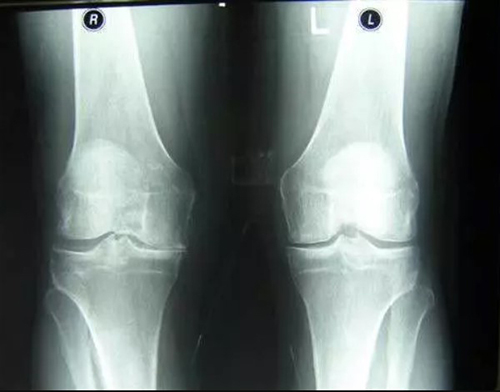

อาการปวดเป็นสัญญาณสำคัญที่บ่งชี้ว่ามีความผิดปกติในข้อ การแค่ทำให้หายปวดจะทำให้สภาพของข้อต่อแย่ลง กระบวนการเสื่อมสภาพจะเร็วขึ้น 3-5 เท่า ส่งผลให้เกิดการเปลี่ยนแปลงที่ย้อนกลับไม่ได้ สูญเสียการเคลื่อนไหวและนำไปสู่การพิการในที่สุด

สาเหตุหลักของโรคข้อ คือการตกตะกอนของผลึกเกลือในข้อ เนื่องจากระบบไหลเวียนโลหิตและของเหลวไขข้อ (synovial fluid) เสื่อมลง:

- แคลเซียมเกาะกระดูก (Osteophytes) คือตัวการของโรคข้อและกระดูกกว่า 97% เช่น โรคข้ออักเสบ โรคข้อเสื่อม โรคกระดูกอ่อน โรคกระดูกพรุน โรคไขข้ออักเสบ โรคถุงน้ำในข้ออักเสบ และแม้แต่ซีสต์ของปมประสาท

เมื่อเกลือเหล่านี้เกาะอยู่บนพื้นผิวของข้อต่อ คราบเกลือเหล่านี้เหมือนกระดาษทรายที่ทำลายเนื้อเยื่อรอบโดยรอบ กระดูก และกระดูกอ่อน เมื่อผลึกโตขึ้น เกลือจะเริ่มทำลายเนื้อเยื่อของกล้ามเนื้อ เอ็น หลอดเลือด และเส้นเลือดฝอย ทำให้เกิดการอักเสบ ติดเชื้อ บวม ก่อให้เกิดการอักเสบและปวดอย่างรุนแรง